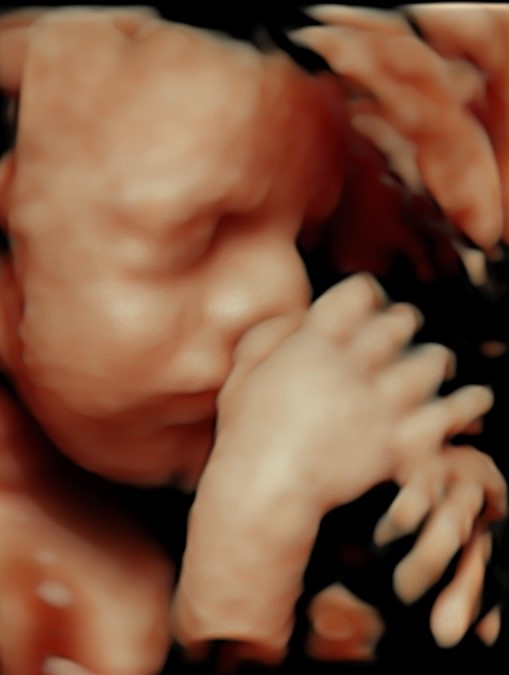

Monmouth County’s First 4D/5D/HD Live Ultrasound Studio

Cherished Memories

4D/5D/HD Ultrasound Gallery